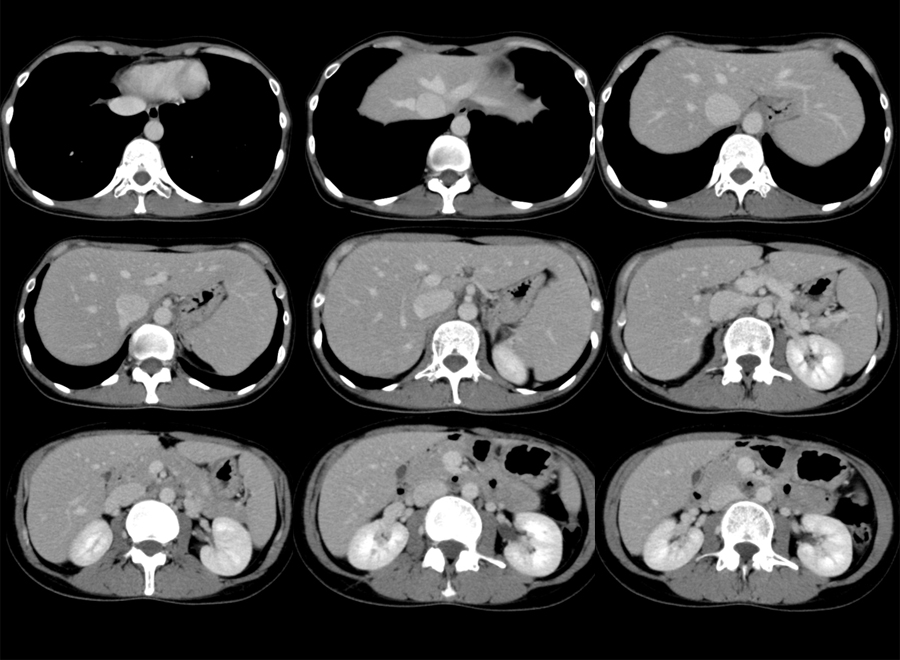

疼痛部のUS T